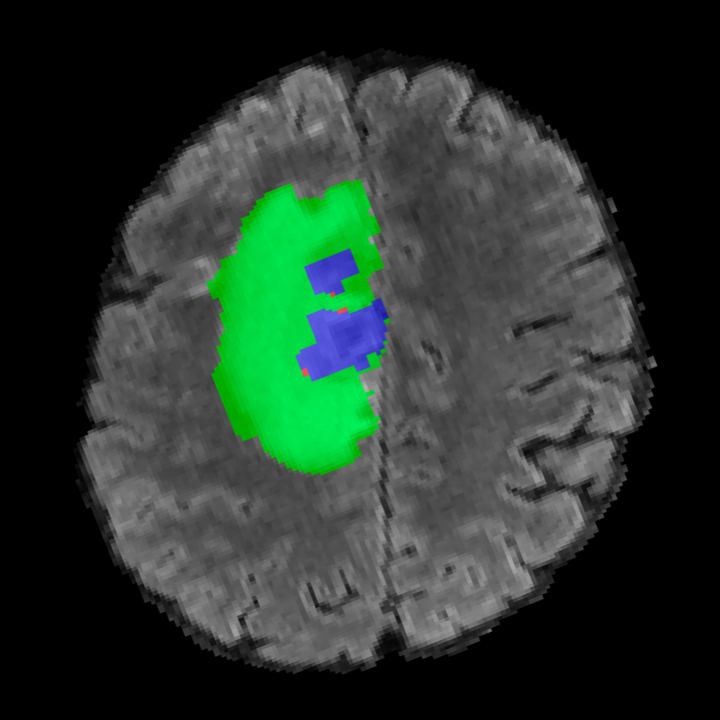

Tumour Information Preservation. For the brain tumor segmentation, we use a Swin UNETR model[28, 70], trained with random rotation, and intensity as data augmentation. On the test set with human ground-truth annotations (), the brain volumes generated from single slice input preserve the volume of the different tumour components (paired t-test, for all 3 classes). In Figure 4, we highlight the tumor profiles of the generated MRIs compared to the ground truth tumour profile. The real MRI Dice score in the test set is 85.15 while the generated MRIs from a single slice have a dice score of 83.09. This shows how the generated MRIs indeed preserve the tumor information and can act as an affordable and informative pseudo-MRI, before conducting an actual costly MRI examination in hospitals. More detailed results are provided in supplementary material.

Leveraging Context. Since we train on a predominantly cancerous brain dataset, one question that might arise is whether X-Diffusion generated MRIs preserve tumour information when the given inputs do not intersect with any tumour. We perform experiments varying the input slice index used to generate the 3D brain MRIs and measure the performance for input slices with no intersection with the tumour (not a single pixel with tumor label in the input slice). We also measure performance when only input slices are selected from tumor range. The Dice Scores of the random slices, no-tumour, and only-tumour are 83.09, 79.23, and 83.68 respectively. As can be seen here, the brain volumes generated from input slices with no tumour still preserve tumour information in reconstructed brain volumes despite a small drop in performance. This indicates that X-Diffusion is leveraging the context to preserve key information, such as tumor locations. This observation is consistent with how tumor segmentation models with global context [13] perform better than local-based U-Nets. More details are provided in supplementary material.